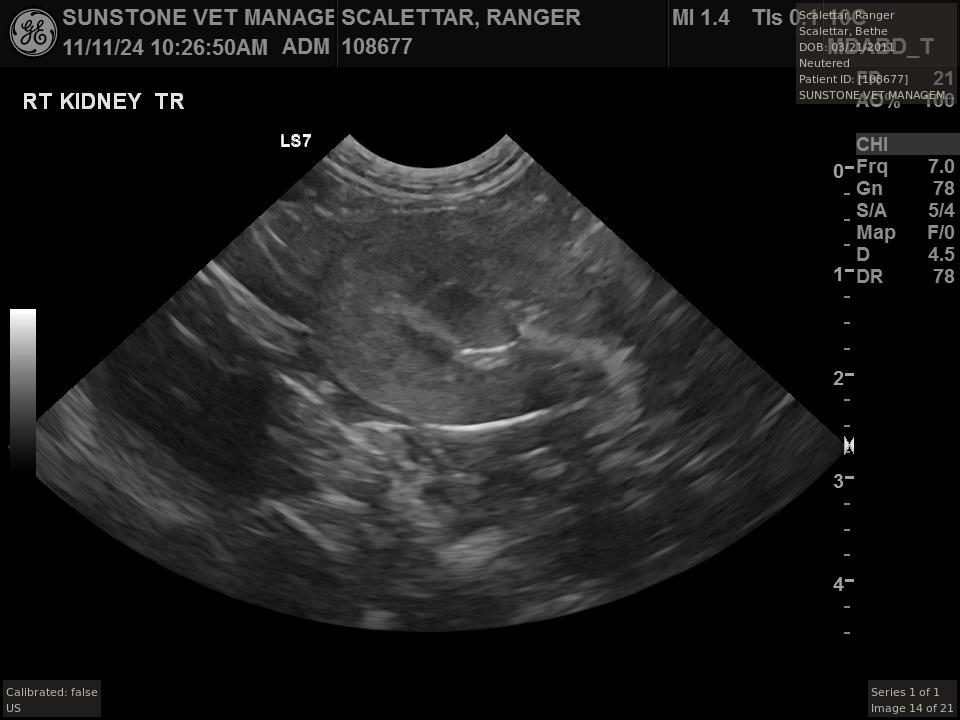

The veterinarian generated a series of images showing different organs and substructures by

changing the position and orientation of the ultrasound transducer. The images were collected

in a defined order, which is repeated from patient to patient, ensuring that nothing is missed. In

Ranger's case, the sonographer collected about twenty images during an examination that

lasted about fifteen minutes.

The sonographer stated that Ranger's ultrasound images were largely normal for an older cat. In particular, they show changes in the kidneys that are commonly noted in geriatric cats and that reflect a risk for the development of chronic kidney disease. However, the images did not show any significant abnormalities in Ranger's stomach, intestines, and associated lymph nodes. Nonetheless, the results did not rule out recurrence of Ranger's small cell lymphoma.